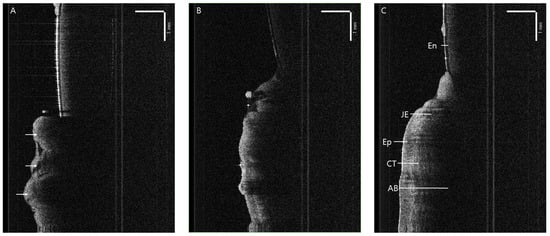

3.3.1. Apically Positioned Flap

Laser

Scalpel